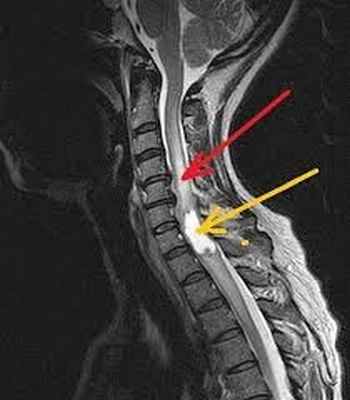

На МРТ снимке, который ниже, видны не только нижнешейный отдел позвоночника, но и грудной. Удачное сочетание, поскольку шейно-грудной переход нередко бывает причиной боли:

При длительных и упорных болевых проявлениях со стороны позвоночника, кроме МРТ шеи иногда приходится делать и МРТ исследование грудного отдела. Это нужно для дифференциальной диагностики. Пример — метастатическое поражение грудного отдела могут давать боли и в шее:

: